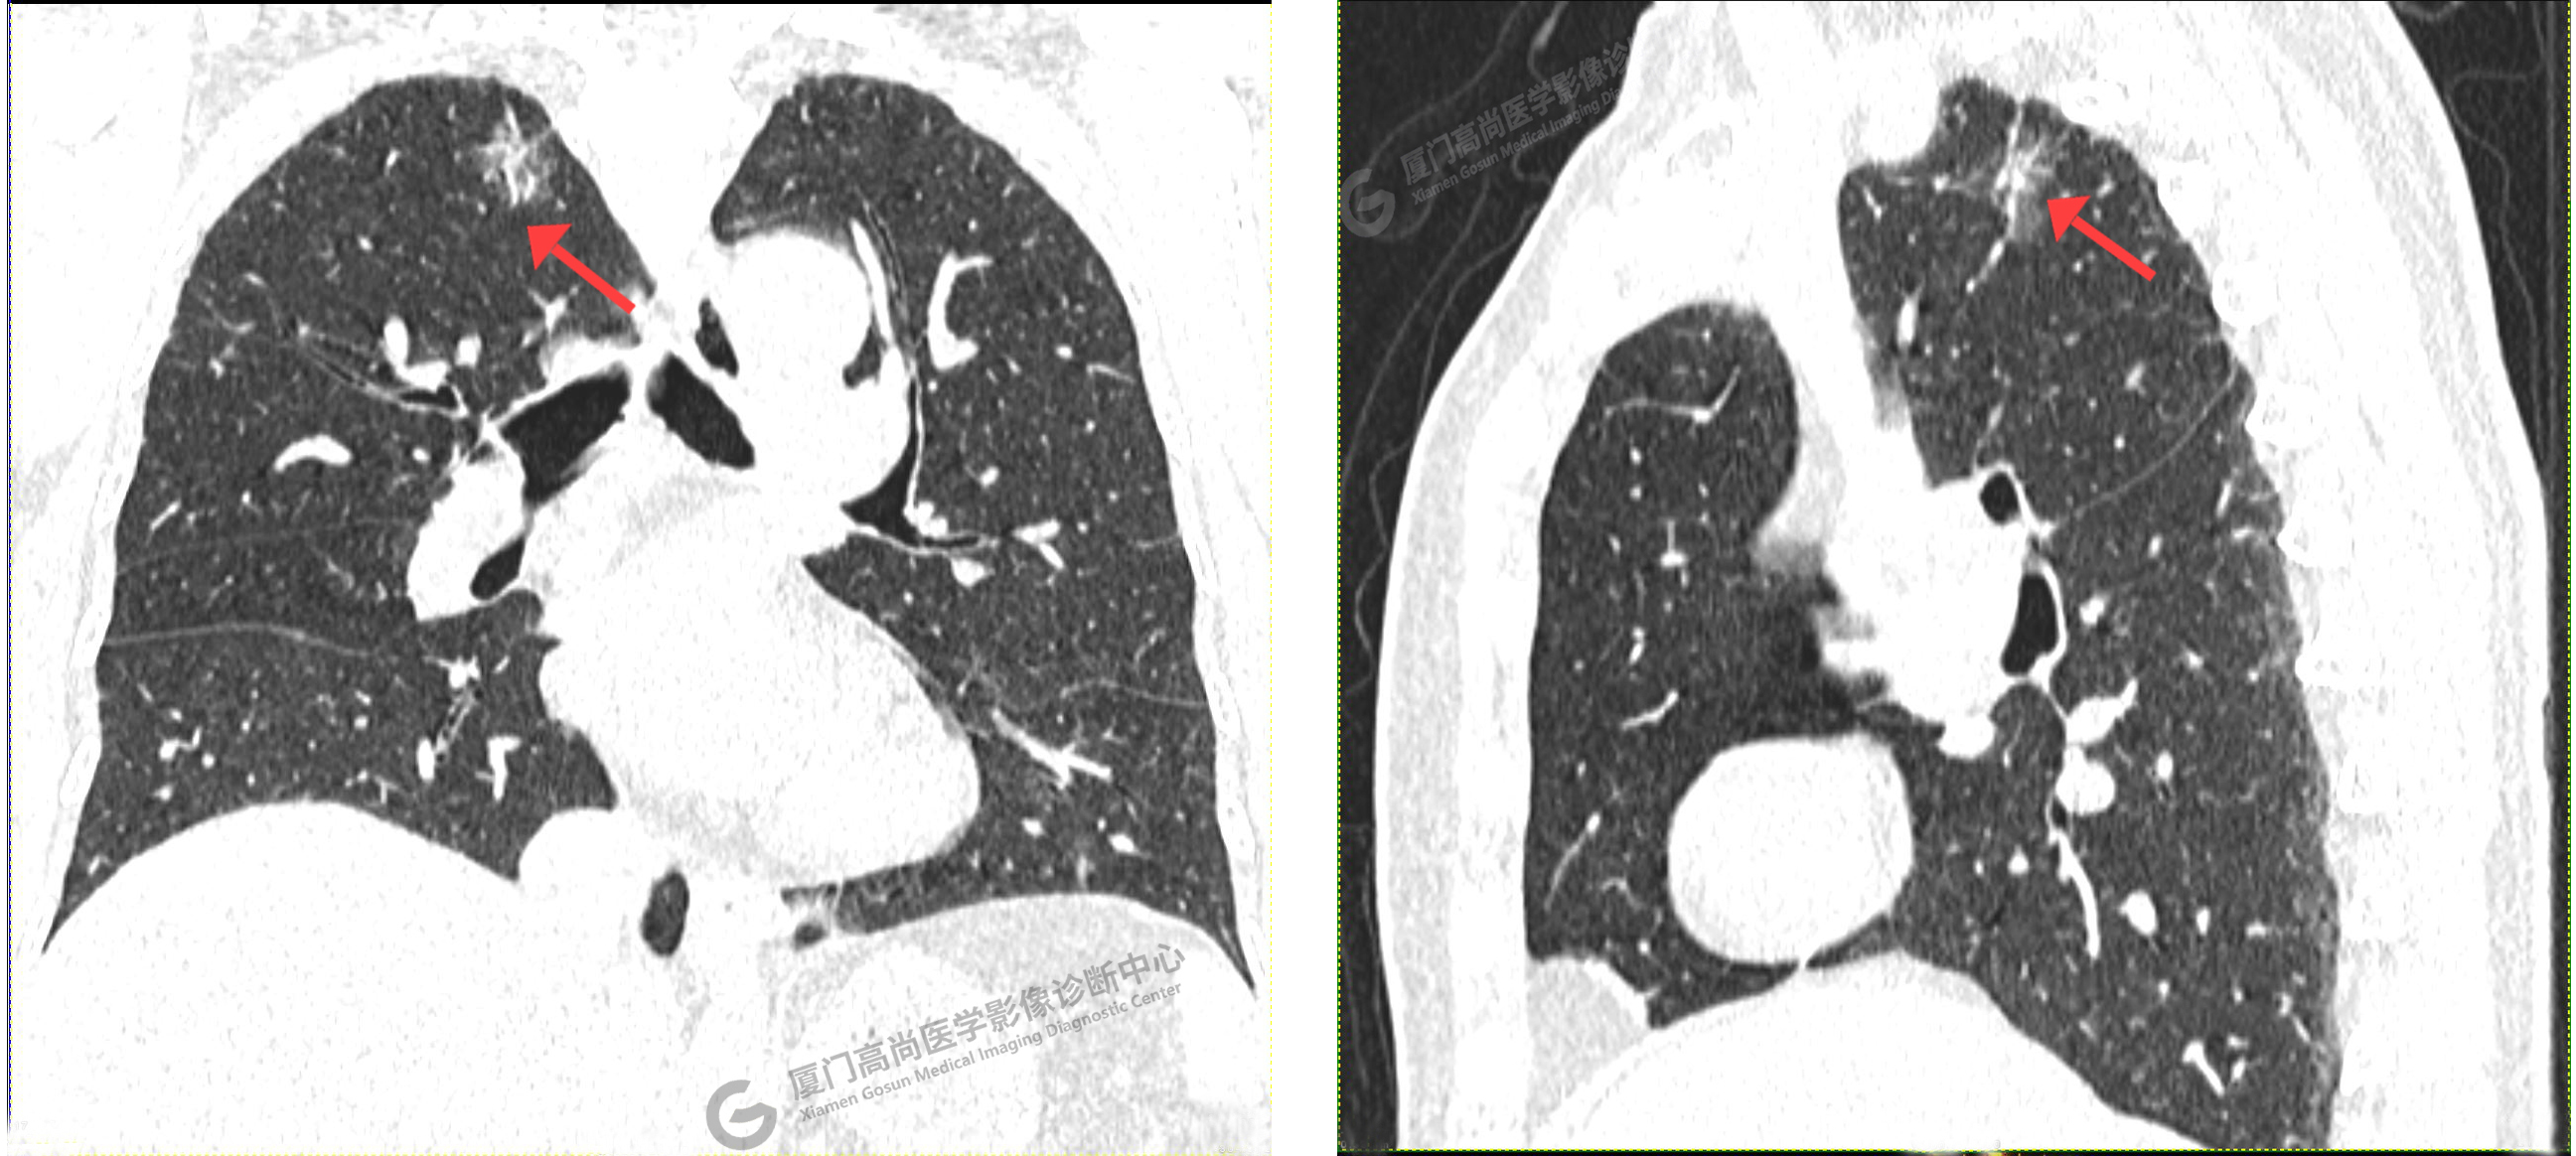

CT影像圖

CT示:右肺上葉尖段磨玻璃結(jié)節(jié),考慮腫瘤性病變可能,建議PET/CT檢查。